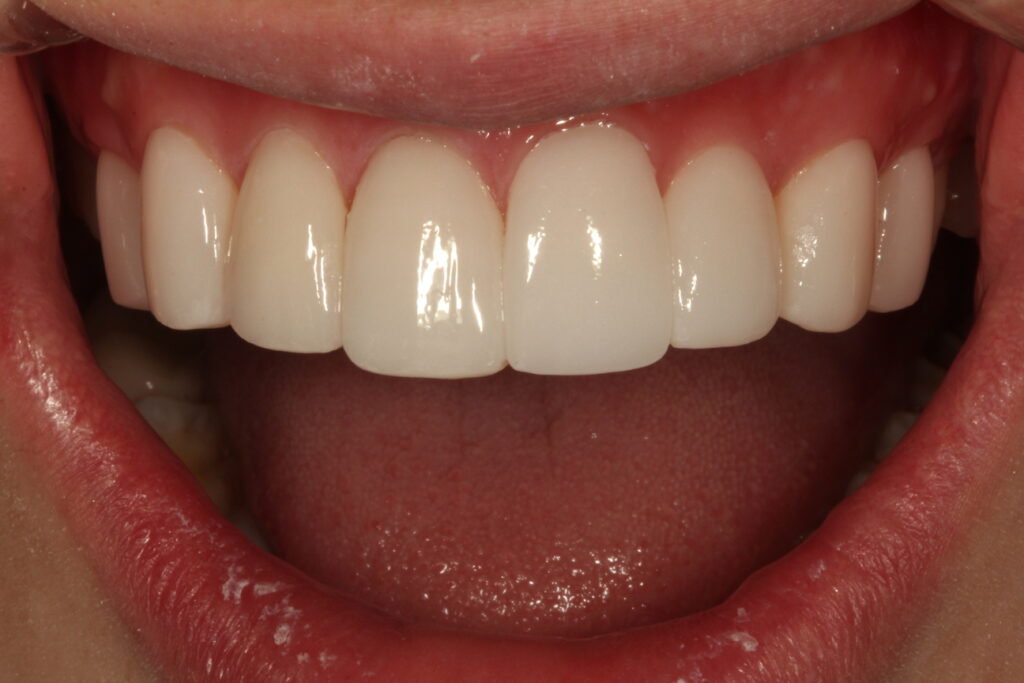

앞니 한 개만 돌출이 되어 웃을 때 신경이 쓰여서 치료받고자 하는 환자였습니다. 이 분은 치아교정이 아닌 단 하루에 치료를 마무리할 수 있는 방법을 선택해서 하루만에 치료를 마무리한 치료전후입니다.

치료후 상태

이 분은 일본에 거주하는 분이었고, 직업이 매일 서비스직종이라 교정기를 하기가 어려웠습니다. 그리고 빠른 치료가 필요한 상태였습니다. 얼굴을 성형할 때에도 필요에 따라서 건강한 뼈를 깍고, 절개를 하기도 합니다. 외모지상주의는 아니지만 컴플렉스가 지나쳐서 사회생활이 어렵다면 이런 치아성형도 좋은 치료가 될 수 있다고 생각합니다.

우선 치료기간이 단 하루면 가능하기 때문에 교정보다 유리합니다. 그리고 교정후 다시 치아가 틀어질까바 보정을 하는 번거로움이 없습니다. 주변의 치아를 같이 라미네이트로 치료할 경우 치아미백 효과까지 볼 수 있습니다.